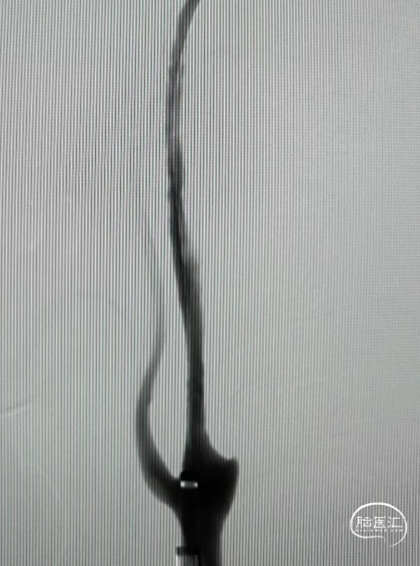

· 加奇生物 Syphonet 4.0*30mm Syphonet®取栓支架

释放4.0*30mm Syphonet®取栓支架

回收4.0*30mm Syphonet®取栓支架

临床获益:1.避免反复交换,精简手术操作,减少手术时间;2.取栓支架远端保护,预防术中栓塞、血栓形成,提高手术安全性;3.Syphonet®取栓支架输送导丝作为工作导丝,提供稳定的系统,近端进行球囊扩张、支架成形、抽吸取栓等一系列操作。

二敬技术——COSIS不是炫技,而是对患者最大限度的保护。Syphonet®取栓支架的闭环设计既能拦截血栓,又为后续操作铺路,这种“一器多用”的智慧,是器械与术式的完美共舞;